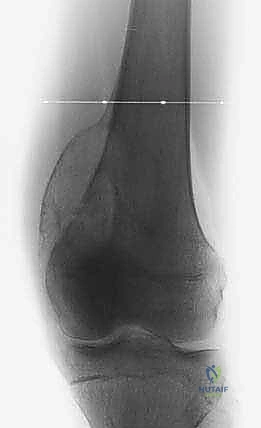

- الأشعة السينية (X-ray): الخطوة الأولى لتقييم العظام وتحديد نمط التدمير العظمي.

- الرنين المغناطيسي (MRI): هو المعيار الذهبي (Gold Standard) لتقييم الأورام. يوضح بدقة امتداد الورم في النخاع العظمي والأنسجة الرخوة، وعلاقته بالأعصاب والأوعية الدموية.

- الأشعة المقطعية (CT Scan): ضرورية لتقييم القشرة العظمية والتكلسات داخل الورم، وللبحث عن أي انتشار في الرئتين.

يعتمد الأستاذ الدكتور محمد هطيف على دراسة هذه الصور الإشعاعية شخصياً قبل تحديد مسار إبرة الخزعة، لضمان عدم تلويث الحجرات العضلية السليمة (Compartments).